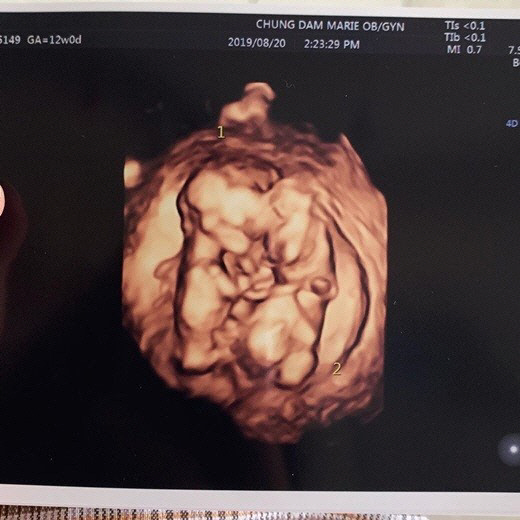

율희는 28일 자신의 SNS에 "짱이의 쌍둥이 동생들 소식 듣고 많은 분들께서 축하해주셔서 너무 감사하다. 요즘 입덧이 너무너무 심해 정신 못 차리고 있는데 그만큼 그 누구보다 고생해주는 남편과 어머님 덕분에 별 탈 없이 행복하게 태교 중이다. 둥이들은 이렇게 서로 꼭 붙어 잘 크고 있다. 다시 한번 축하해주셔서 감사하다"고 밝혔다.

둥이들은 이렇게 서로 꼭 붙어 잘 크고 있답니다. 다시 한번 축하해주셔서 감사드려요.